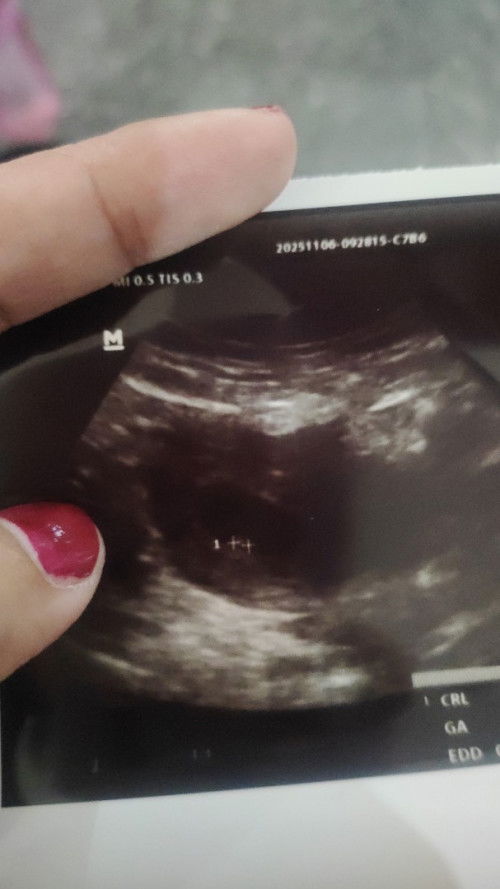

aku 6 minggu ke gini bun

saya kya gini bun 6 minggu